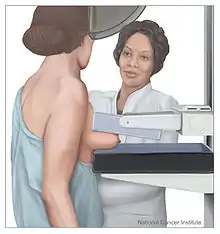

Screening

Breast cancer screening refers to testing otherwise-healthy women for breast cancer in an attempt to diagnose breast tumors early when treatments are more successful. The most common screening test for breast cancer is low-dose X-ray imaging of the breast, called mammography.[113] Each breast is pressed between two plates and imaged. Tumors can appear unusually dense within the breast, distort the shape of surrounding tissue, or cause small dense flecks called microcalcifications.[114] Radiologists generally report mammogram results on a standardized scale – the six-point Breast Imaging-Reporting and Data System (BI-RADS) is the most common globally – where a higher number corresponds to a greater risk of a cancerous tumor.[115][116]

A mammogram also reveals breast density; dense breast tissue appears opaque on a mammogram and can obscure tumors.[117][118] BI-RADS categorizes breast density into four categories. Mammography can detect around 90% of breast tumors in the least dense breasts (called "fatty" breasts), but just 60% in the most dense breasts (called "extremely dense").[119] Women with particularly dense breasts can instead be screened by ultrasound, magnetic resonance imaging (MRI), or tomosynthesis, all of which more sensitively detect breast tumors.[120]

Regular screening mammography reduces breast cancer deaths by at least 20%.[121] Most medical guidelines recommend annual screening mammograms for women aged 50–70.[122] Screening also reduces breast cancer mortality in women aged 40–49, and some guidelines recommend annual screening in this age group as well.[122][123] For women at high risk for developing breast cancer, most guidelines recommend adding MRI screening to mammography, to increase the chance of detecting potentially dangerous tumors.[120] Regularly feeling one's own breasts for lumps or other abnormalities, called breast self-examination, does not reduce a person's chance of dying from breast cancer.[124] Clinical breast exams, where a health professional feels the breasts for abnormalities, are common;[125] whether they reduce the risk of dying from breast cancer is not known.[113]

For the average woman, the U.S. Preventive Services Task Force and American College of Physicians recommends mammography every two years in women between the ages of 50 and 74,[12][126] the Council of Europe recommends mammography between 50 and 69 with most programs using a 2-year frequency,[127] while the European Commission recommends mammography from 45 to 75 every 2 to 3 years,[128] and in Canada screening is recommended between the ages of 50 and 74 at a frequency of 2 to 3 years.[129] The American Cancer Society also endorses that women ages 40 and older receive mammograms annually.[130] These task force reports point out that in addition to unnecessary surgery and anxiety, the risks of more frequent mammograms include a small but significant increase in breast cancer induced by radiation.[131]